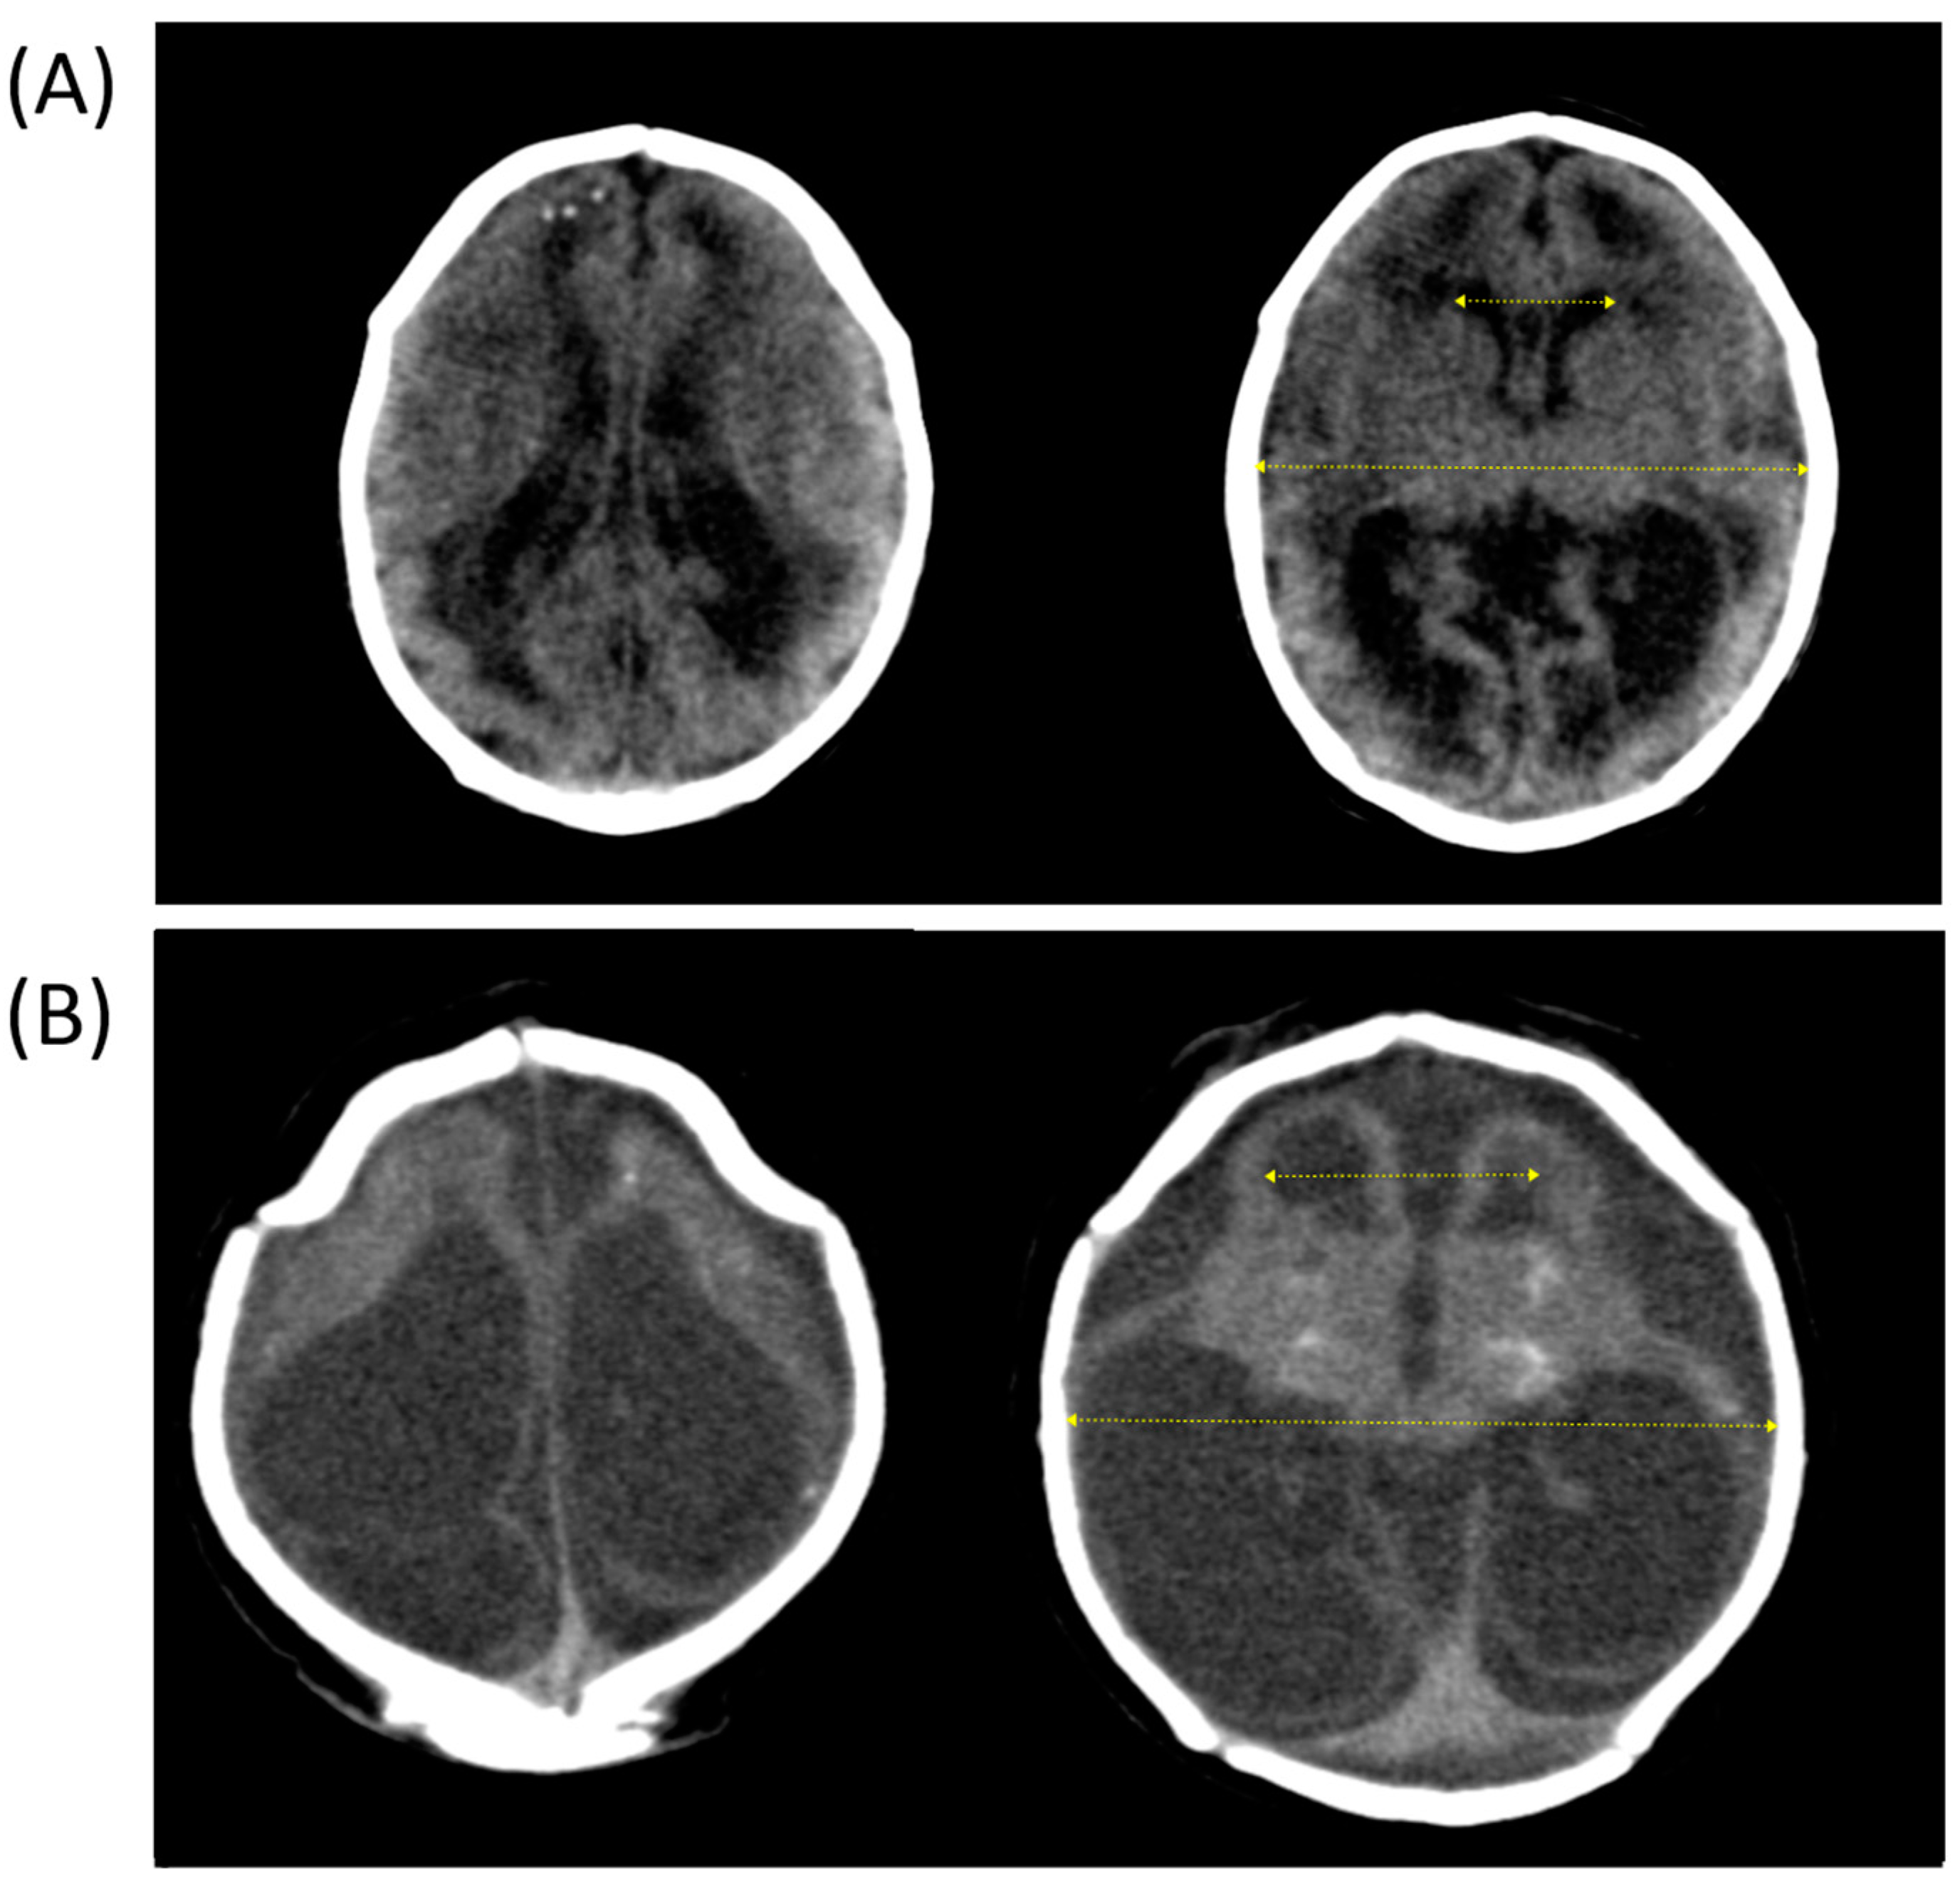

- Evans, W.A. An encephalographic ratio for estimating ventricular enlargement and cerebral atrophy. Arch. Neurol. Psychiatry 1942, 47, 931–937. [Google Scholar] [CrossRef]

- Gawler, J.; Du Boulay, G.H.; Bull, J.W.D.; Marshall, J. Computerized tomography (the EMI scanner): A comparison with pneumoencephalography and ventriculography. J. Neurol. Neurosurg. Psychiatry 1976, 39, 203–211. [Google Scholar] [CrossRef] [PubMed]

- Ragan, D.K.; Cerqua, J.; Nash, T.; McKinstry, R.C.; Shimony, J.S.; Jones, B.V.; Mangano, F.T.; Holland, S.K.; Yuan, W.; Limbrick, D.D. The accuracy of linear indices of ventricular volume in pediatric hydrocephalus: Technical note. J. Neurosurg. Pediatr. 2015, 15, 547–551. [Google Scholar] [CrossRef]

- Sarı, E.; Sarı, S.; Akgün, V.; Özcan, E.; Ìnce, S.; Babacan, O.; Saldır, M.; Açıkel, C.; Başbozkurt, G.; Yeşilkaya, Ş. Measures of ventricles and evans’ index: From neonate to adolescent. Pediatr. Neurosurg. 2015, 50, 12–17. [Google Scholar] [CrossRef]

- Von Bezing, H.; Andronikou, S.; Van Toorn, R.; Douglas, T. Are linear measurements and computerized volumetric ratios determined from axial MRI useful for diagnosing hydrocephalus in children with tuberculous meningitis? Child’s Nerv. Syst. 2012, 28, 79–85. [Google Scholar] [CrossRef]

- Wilk, R.; Kluczewska, E.; Syc, B.; Bajor, G. Normative values for selected linear indices of the intracranial fluid spaces based on CT images of the head in children. Pol. J. Radiol. 2011, 76, 16–25. [Google Scholar]

- Missori, P.; Rughetti, A.; Peschillo, S.; Gualdi, G.; Di Biasi, C.; Nofroni, I.; Marinelli, L.; Fattapposta, F.; Currà, A. In normal aging ventricular system never attains pathological values of evans’ index. Oncotarget 2016, 7, 11860–11863. [Google Scholar] [CrossRef]

| Evans’ index ‡ | 0.39 [0.35–0.44] |

| Ventriculomegaly | 39 (78) |